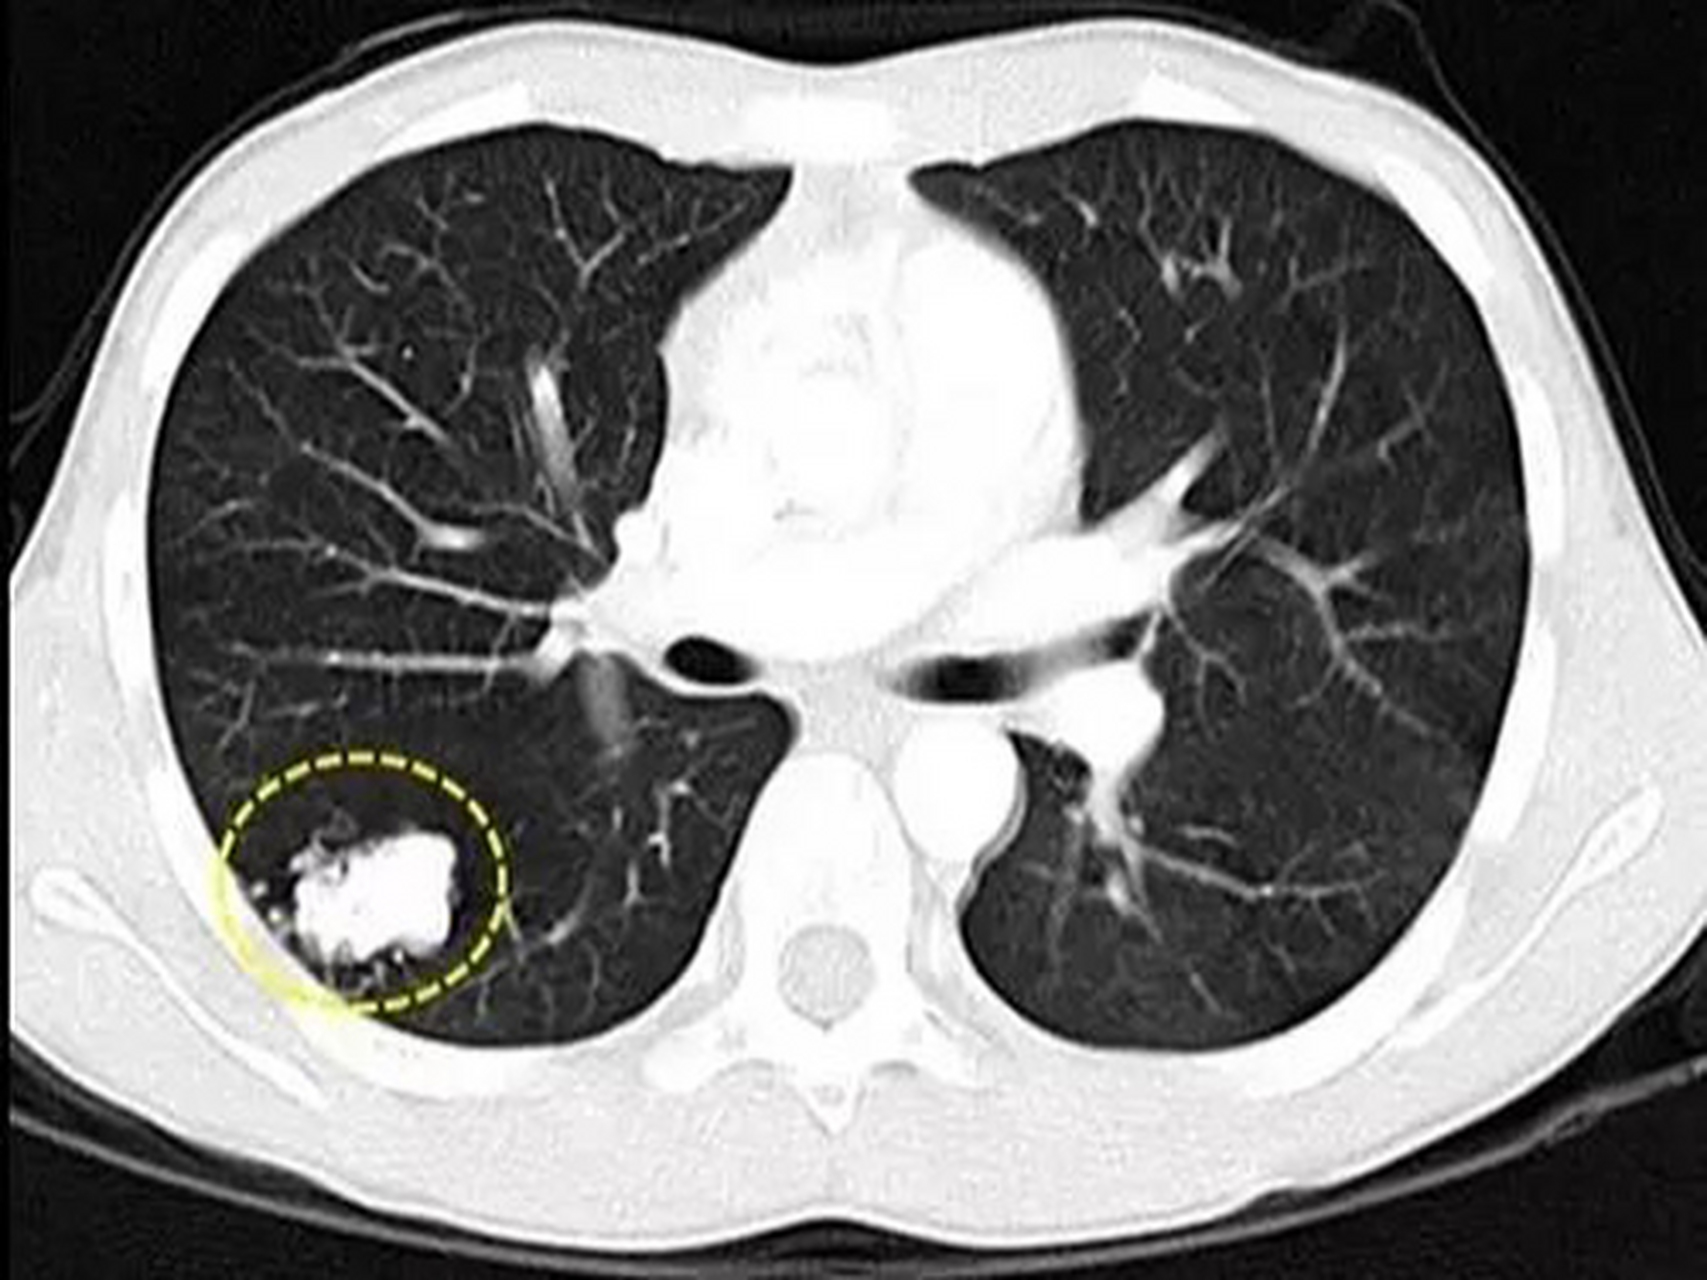

查出肺纤维灶,跟踪4年半,长成肺腺癌

图片尺寸780x421